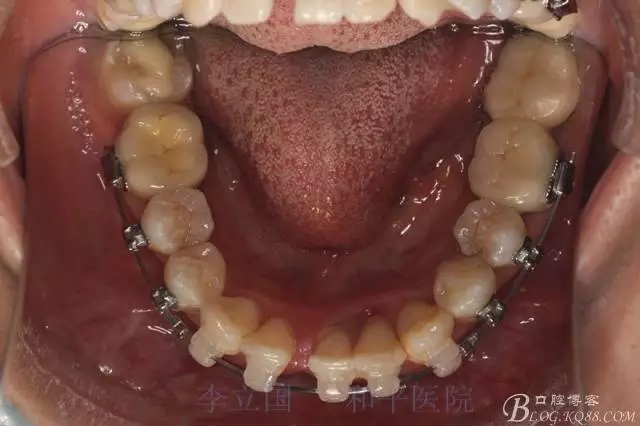

1.拔除14、24、31。

2.磨牙關(guān)系一側(cè)完全遠(yuǎn)中,一側(cè)遠(yuǎn)中尖対尖,采用兩個上4,一個下1的拔牙模式。